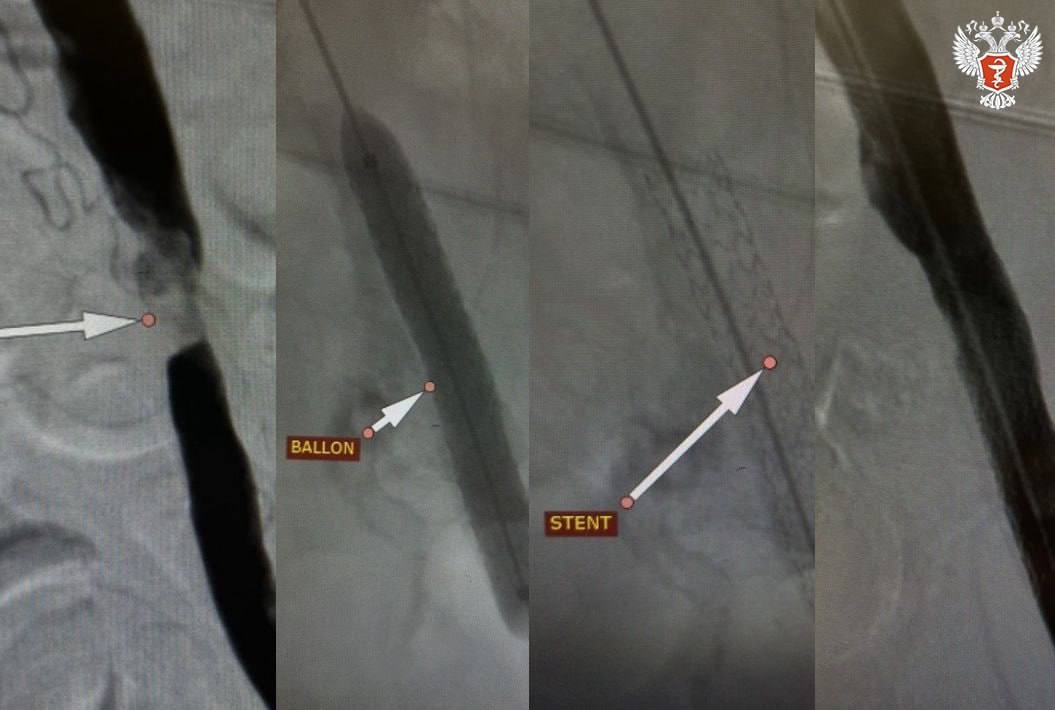

Во время операции специалисты через небольшой прокол ввели в суженный сосуд специальный баллон, расширили его, чтобы восстановить кровоток, а затем установили в это место металлический каркас — стент. Он служит опорой и не дает сосуду снова сузиться.

— Мы выполнили стентирование подвздошной артерии, которое позволило быстро нормализовать кровообращение в нижней конечности, — рассказал заведующий отделением рентгенохирургических методов диагностики и лечения Андрей Легкий.